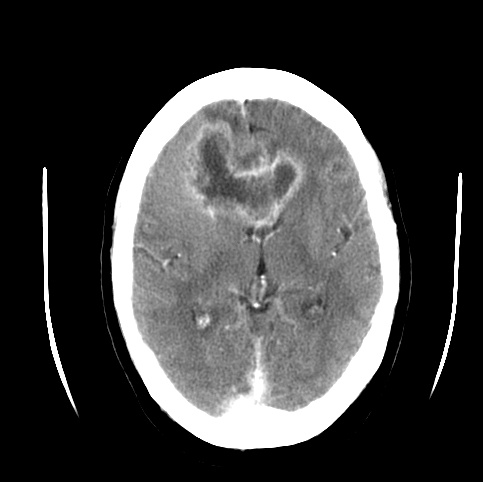

Glio: The CT/MRI findings of a butterfly appearance with central necrosis is classic for GBM, and the heterogenous, serpiginous contrast enhancement is typical of high-grade.

CT scan characteristically shows numerous minute punctate hemorrhages with blurring of grey white interface.